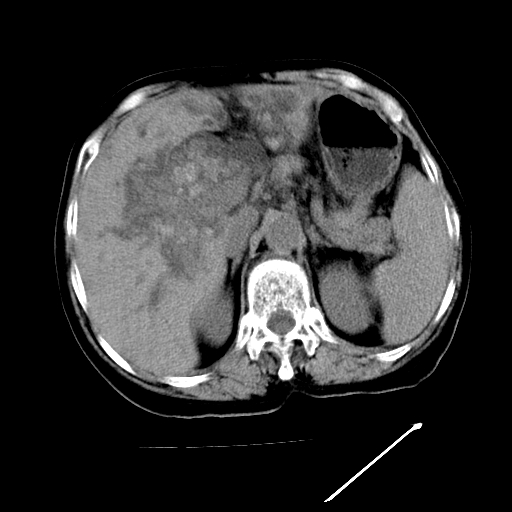

以下是引用卜一在2009-4-7 5:06:00的发言:[br]左右肝内胆管结石伴扩张合并胆系感染;不除外胆管细胞癌可能。支持! [br] [br]

以下是引用随光逐影在2009-4-7 8:21:00的发言:[br]肝内外胆管多发性结石并肝内外胆管扩张;胆系感染。